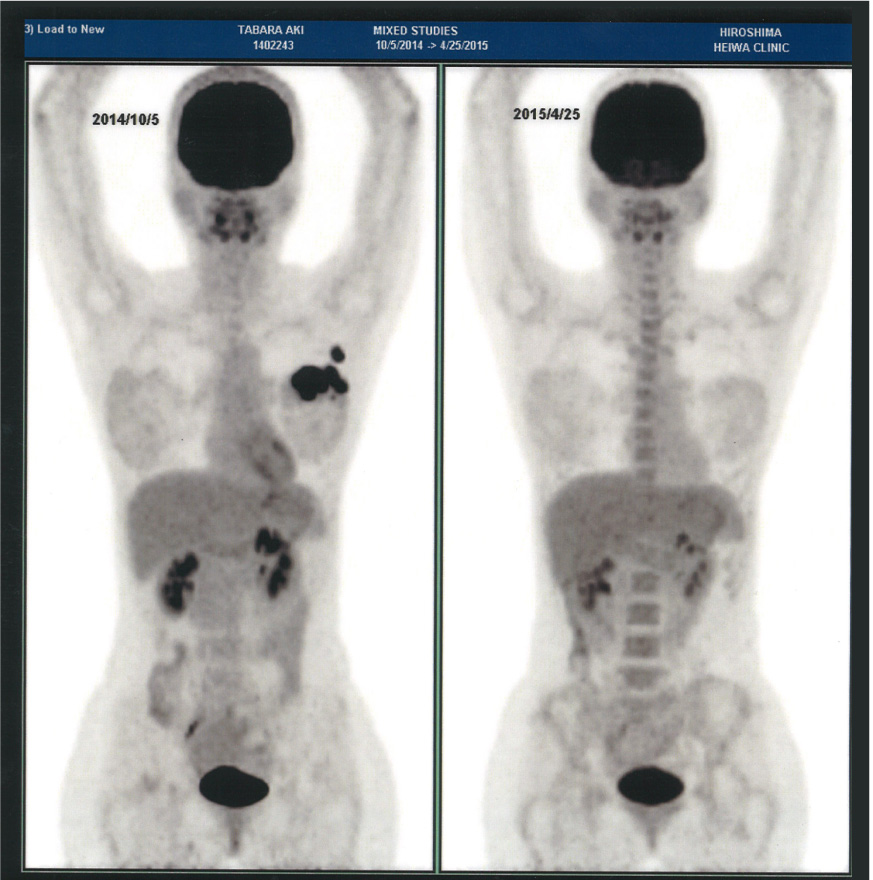

左が治療前、右が治療後の画像。左胸の黒い影がなくなっていることがわかります

治療を続けながらそんな日々を過ごしていると、もちろん抗癌剤が身体に合ったことも大きいのですが、3ヶ月後には癌がなくなっていました。自身でも負の感情を排出してやりきった感があり、もう大丈夫と思えたのですが、夫や周囲に勧められ「それでみんなが安心するなら」と左胸の摘出手術を受けました。